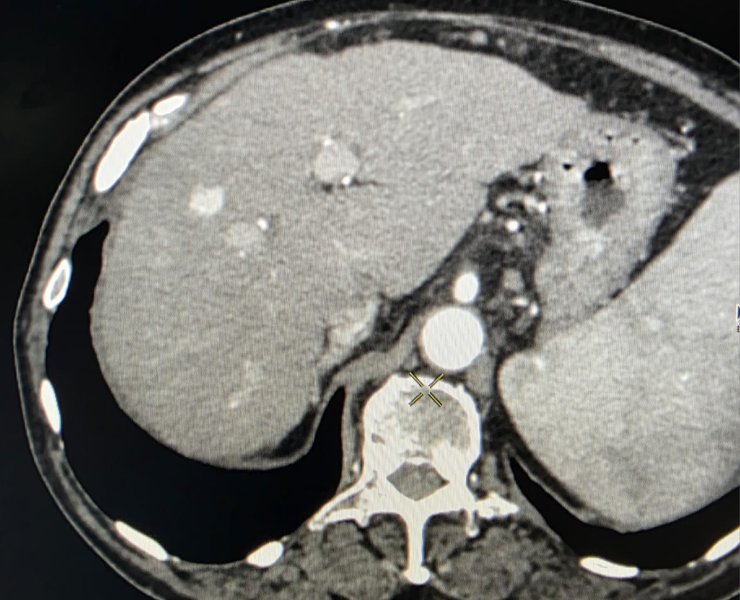

Microwave ablation of liver cancers

Liver tumor

- Thermal ablation (radiofrequency or microwave): destroys tumour tissue by heating it from within through a thin needle placed under USG/CT guidance.

Insertion of microwave needle treatment of cancer